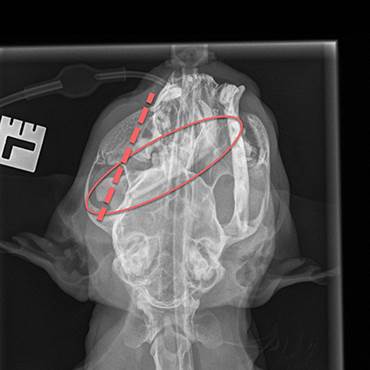

“Poor Loopie was in a critical condition when he came into the Pet Hospital,” said PDSA Vet Jane Sedgewick. “He was suffering from severe head trauma and had a swelling that changed the shape of the top of his head. He also had a heavy nose bleed and the road had ripped away the skin from his lower jaw, which was also clearly broken through the middle. X-rays later revealed he had broken his jaw in several places.”

Vet Jane added: “We performed surgery to wire his jaw back together, re-attached the skin over his chin and placed a feeding tube into his throat. Despite his injuries, he did amazingly well and, after twelve days of intensive, round-the-clock nursing care he was able to finally go home.